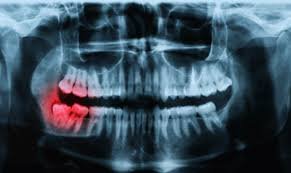

Full Mouth X-Ray (OPG)

Our advanced OPG X-ray provides a panoramic view of your entire jaw, helping in the accurate diagnosis of dental conditions. Essential for orthodontic planning, implant placement, and detecting hidden oral health issues.

Dental X-Ray

High-resolution digital dental X-rays ensure precise detection of cavities, infections, and bone loss. Safe, quick, and effective, they help in early diagnosis for better treatment outcomes.